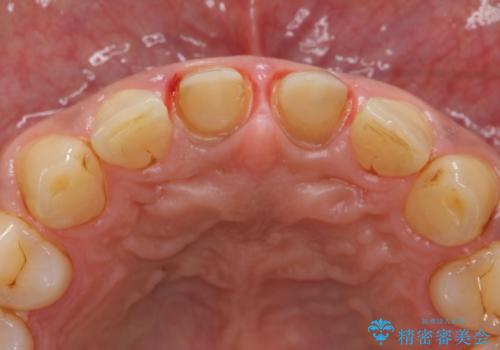

歯ぐきからの出血 膿が出る 前歯根管・セラミック治療

- 体調により前歯部の歯ぐきから出血や膿が出ることの改善を求めて来院されました。

X線写真より、根尖部に透過像が認められ根管治療・ファイバーコア築盛・セラミッククラウンの作製が必要な状態です。

- 46万円(仮歯・根管治療・ファイバーコア・ジルコニアクラウン×2)費用は治療当時の料金となります